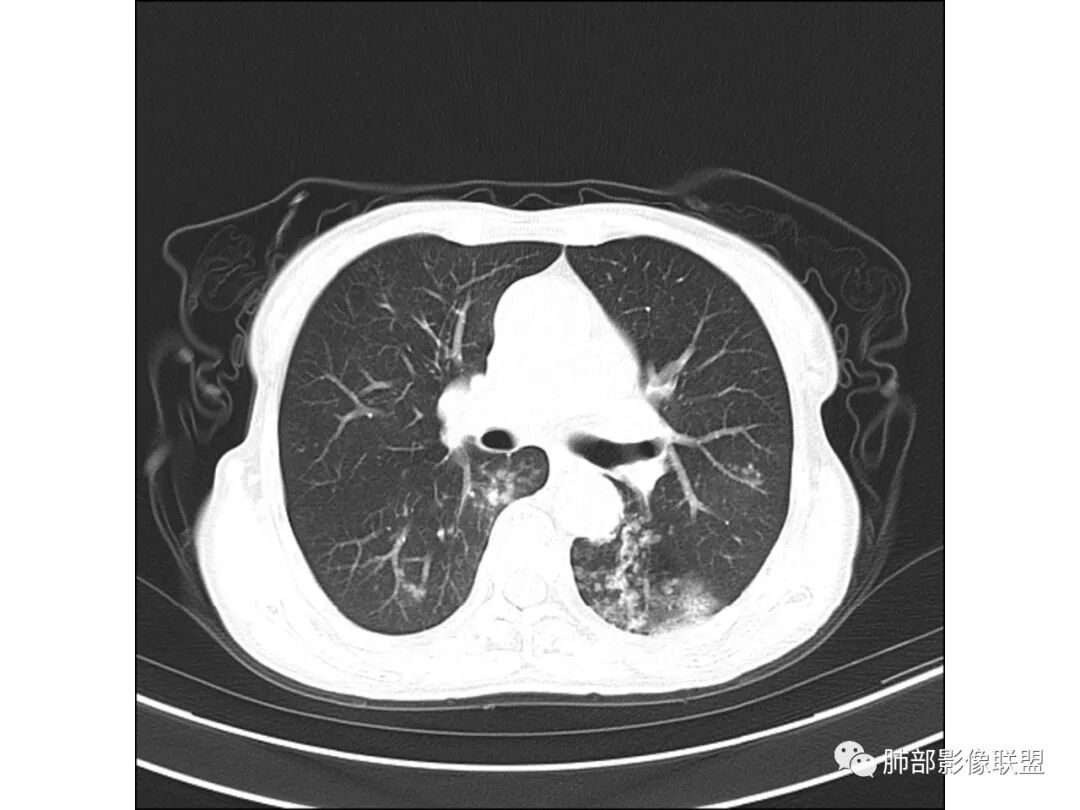

慢性迁延不愈患者 发热伴脓痰 双肺多发小结节伴磨玻璃影 左肺下叶体积缩小 支气管扩张伴实变 实变内支气管不规则 平扫密度尚均较肌肉稍低 支气管扩张感染基础上合并淋巴瘤待查 建议增强穿刺

老年女性,慢性病程,有反复咯血、发热,左下胸廓塌陷,双肺下叶多发片状实变影,伴多发结节,左下肺实变为主伴卫星灶,支气管扩张,伴虫噬样空洞及支气管壁钙化,首先考虑结核,鉴别粘液腺癌

老年丶反复发作2年,但双肺下叶多发腺泡结节,延气道分布,影像不符合陈旧病变,左下实变影,伴牵拉支扩,考虑慢性病变首先考虑吸入性肺炎,建议结合病史是否有隐性误吸,可查胃镜、气管镜丶钡透,除外食管、气管瘘。鉴别腺癌丶放线菌丶努卡菌丶NTM

患者老年女性,反复咳嗽 咳痰 活动后胸闷 气短,胸ct:病变以左肺下叶体积缩小,呈大片实变,实变组织内可见 左肺下叶支气管开口扩张,右肺下叶背段多发结节样病灶,周围有毛玻璃影。良性考虑感染性病变,ABPA ?结核?;恶性考虑:粘膜相关淋巴瘤。

双肺多叶段多发腺泡结节,延气道分布,双下肺为诸,左下肺大片实变影,伴牵拉支扩,老年人首先考虑支气管肺炎。鉴别腺癌。

双下肺多发腺泡结节,左肺下叶实变,彭隆,结核伴感染,鉴别结核伴粘液腺癌。

双肺下叶多发片,结节,左下肺实变,局部膨隆,粘液腺癌?鉴别结核。

晨读病例,老年女性,病程长,左侧胸廓缩小,双下肺叶多发片状实变影,伴多发结节及树芽征,左下肺实变,有坏死空洞,支气管扩张壁增厚有钙化,考虑结核,鉴别粘液腺癌,淋巴瘤,排除异物

大家看看这支气管

这些支气管扩张

支气管扩张、扭曲成团,附近钙化灶

这例左下叶的体积是整体缩小的,左下叶的支气管主干稍微小一点点,然后左上叶的下舌段也有类似的病灶,然后我们看到一团乱的支气管扩张,但它有特点,边缘凹凸不平。那什么样的支气管扩张边缘会如此凹凸不平呢,等我截个图:

首先这幅图支气管很多地方是扭曲的,远端扩张的特别厉害。如果是肿瘤,首先考虑淋巴瘤,因为支气管可直达远端,稍扩张,但是它的前提是周围要实性占位的,而且它不会这样扭曲变形。我们看这个病例的支气管扩张,它支气管扩张占大部分区域,中间稍有些实性的结构,这就不符合了。这幅图你会发现所有支气管都是扩张的,实性部分偏少,外围胸水。所以我更倾向慢性炎性病变,能够引起支气管扩张的炎性病变有哪些?结核?NTM?支扩伴感染?大方向是慢性炎性病变。这些左下肺播散出来的病灶,咳中等量黄浓痰,我考虑还可能合并细菌感染。

1.双肺斑片影、大小不等结节影,边界不清,密度较均一,钙化不多见,可见树丫。

2.左肺下叶大范围病灶,其间柱状支气管扩张相当显眼。

这些都支持慢性炎性改变。

3.我们知道继发性肺结核为典型的慢性消耗性疾病,较少出现高热及较大量浓痰。该患者病灶密度较均一,新旧不等的特点并不突出,缺少高密度区,双肺上叶比较干净,夸张的支扩也有别于结核病灶导致的“鸡爪样”改变。